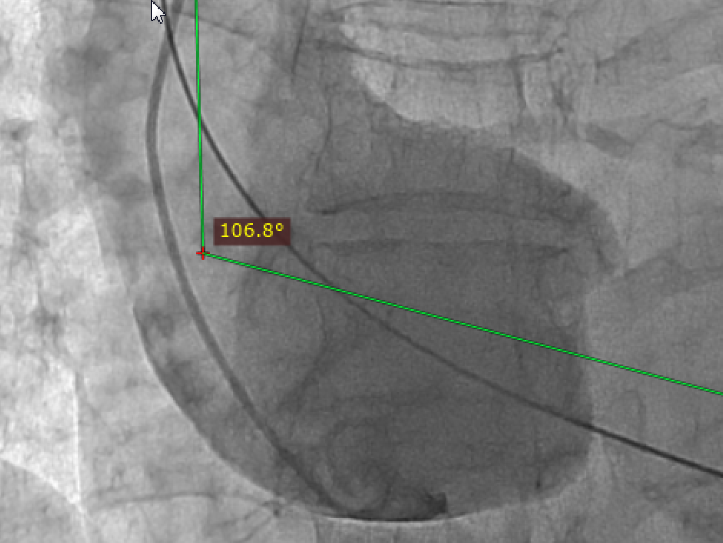

升主动脉与主动脉窦部夹角:106°

图3 主动脉瓣大量反流;主动脉瓣环平面几乎与脊柱平行